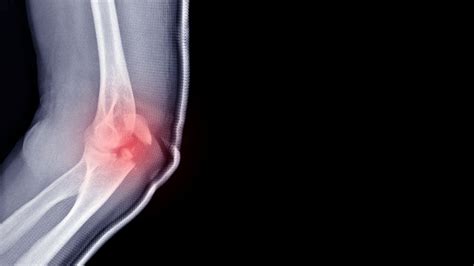

Symptoms of Elbow Hairline Fractures

Recognizing the symptoms of an elbow hairline fracture is essential for prompt treatment. Common symptoms include:

• Pain: Persistent pain in the elbow, which may worsen with movement or pressure.

• Swelling: Swelling around the elbow joint, which can make it difficult to move the arm.

• Bruising: Bruising or discoloration around the elbow area.

• Tenderness: Tenderness to touch, especially over the affected bone.

• Limited Range of Motion: Difficulty moving the elbow or arm due to pain and swelling.